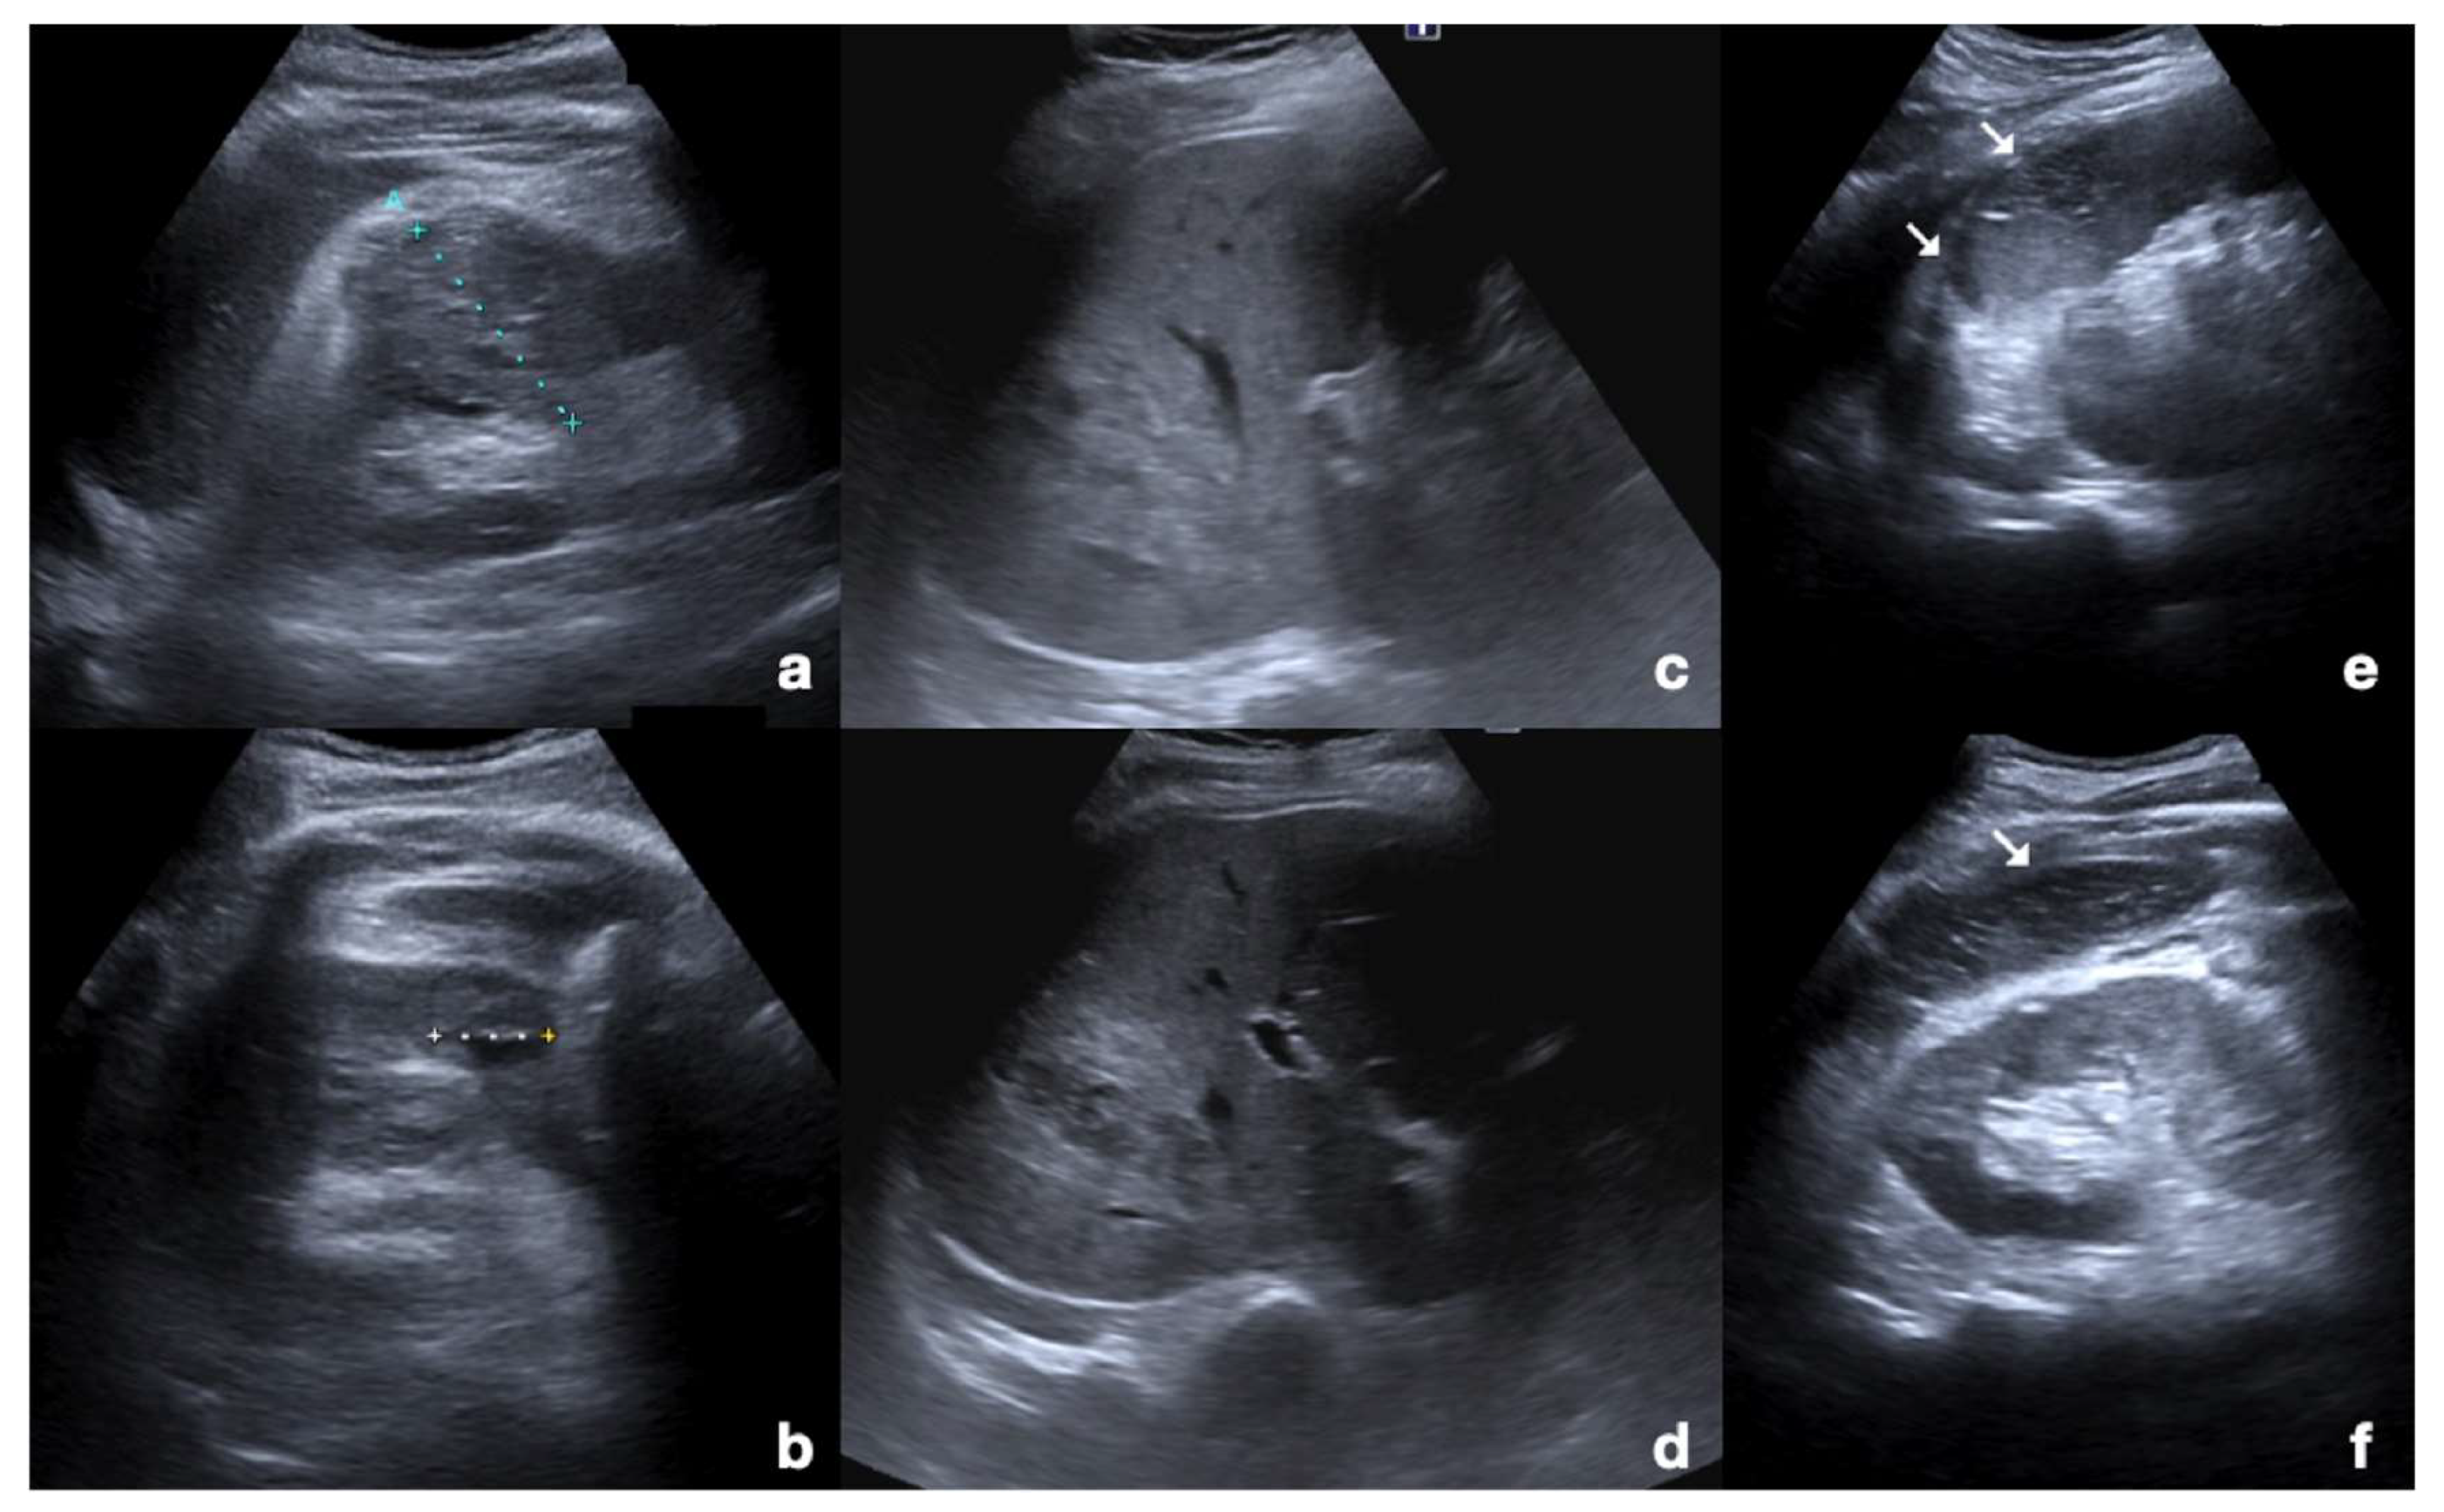

2.3.1. Solid Organ Injuries May Involve the Parenchyma and the Vessel

- Parenchymal injuries:

2.3.2. Vascular Injuries